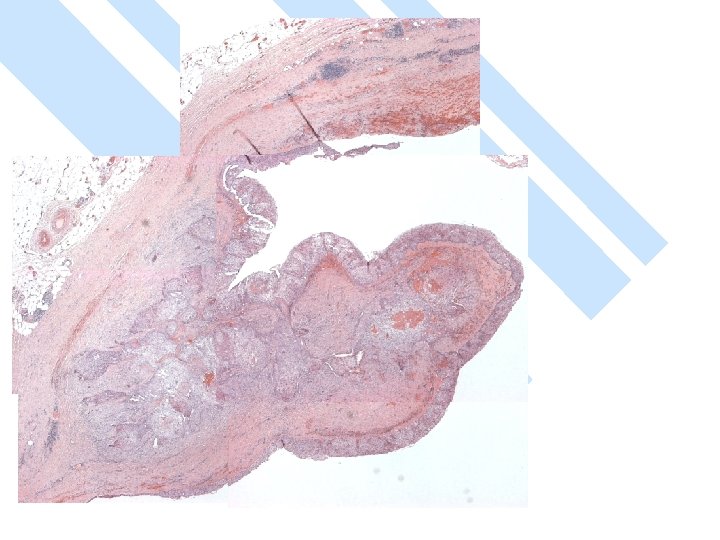

Gross: -A ruptured cyst with attached breast tissue measuring 8. 5 x 6 x 2. 8 cm - area of hemorrhage in cyst wall

Gross n Size: – vary 1 -10 cm – > 50% > 5 cm – Larger than other types of breast cancer. n Cystic > 50%

Micro n Exclude metastasis – Most common sites: lung, uterine cervix, urinary bladder. – Cystic degeneration NOT seen in metastatic carcinoma

Micro The strongest evidence of a primary SCC of breast is presence of in-situ squamous carcinoma in duct or cyst lining.